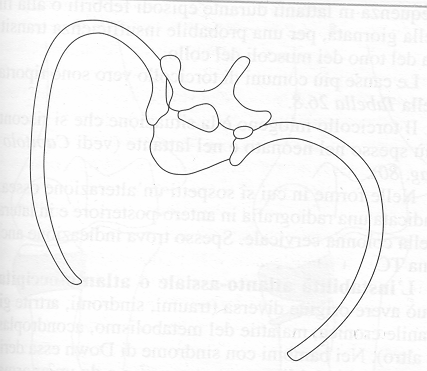

Figura

4. I pedicelli dell'arco vertebrale

A. Radiografia

posteriore-anteriore preoperatoria; B. Radiografia laterale

preoperatoria; C. Radiografia posteriore-anteriore postoperatoria; D.

Radiografia laterale postoperatoria.

Gli

interventi sono in generale attuati per via posteriore (Figura

3 e Figura 4). La via anteriore viene

usata principalmente per curve isolate toraciche e lombari (Figura

A.

Radiografia laterale preoperatoria; B. Radiografia

posteriore-anteriore preoperatoria; C. Radiografia laterale

postoperatoria; D. Radiografia posteriore-anteriore postoperatoria.

Figura

6. Radiografia di un adolescente con scoliosi toracica idiopatica

trattata chirurgicamente per via anteriore.

A.

Radiografia laterale preoperatoria; B. Radiografia

posteriore-anteriore preoperatoria; C. Radiografia laterale

postoperatoria; D. Radiografia posteriore-anteriore postoperatoria.